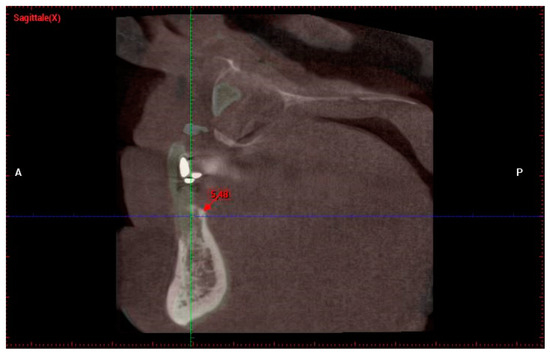

- Measurement in mm of the depth of insertion of the instrument into the gingival sulcus;